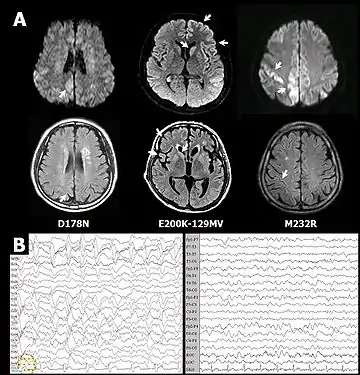

- Choi B.Y., Kim S.Y., Seo S.Y., An S.S., Kim S., Park S.E., Lee S.H., Choi Y.J., Kim S.J., Kim C.K., Park J.S., Ju Y.R. Mutations at codons 178, 200-129, and 232 contributed to the inherited prion diseases in Korean patients (англ.) // BMC Infect. Dis. : journal. — 2009. — Vol. 9. — P. 132. — doi:10.1186/1471-2334-9-132. — PMID 19698114.